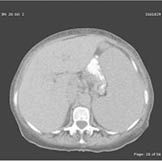

FIGURE 1

CT Scan of the Abdomen-Computed tomography (CT) scan of the abdomen showing a mass in the gastric antrum, massive splenomegaly, and extensive lymphadenopathy.

She was admitted to the intensive care unit in February 2007 and was initially thought to have GI bleeding secondary to thrombocytopenia, and platelet dysfunction secondary to MDS. She received a platelet transfusion. Because of the abdominal pain, splenomegaly, and low hematocrit on the initial presentation, a computed tomography scan of the abdomen was performed, showing a 6.4 - 5.5 cm mass in the gastric antrum, massive splenomegaly of 21.5 - 8.5 cm, and extensive lymphadenopathy (Figure 1).